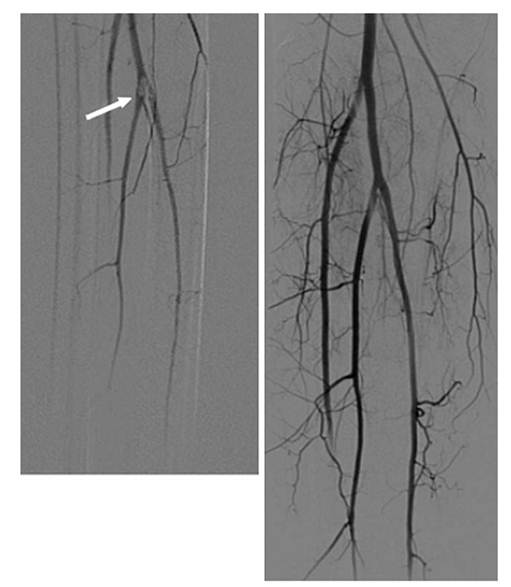

An arteriogram representing an embolus is shown in Fig. 3.

Fig. 3. Embolus lodged at the origins of the calf vessels (arrow).

Angiograms display ilms before and after thrombolysis

Angiographic signs of embolism are an abrupt, convex start of the occlusion and lack of collaterals. Thrombosis is likely when the arteriogram shows well-developed collaterals and atherosclerotic changes in other vascular segments.